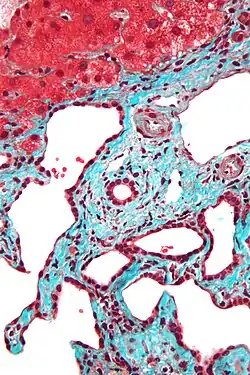

Micrograph of a bile duct hamartoma. Trichrome stain. Intermediate magnification -

Micrograph of a bile duct hamartoma. Trichrome stain, high magnification -